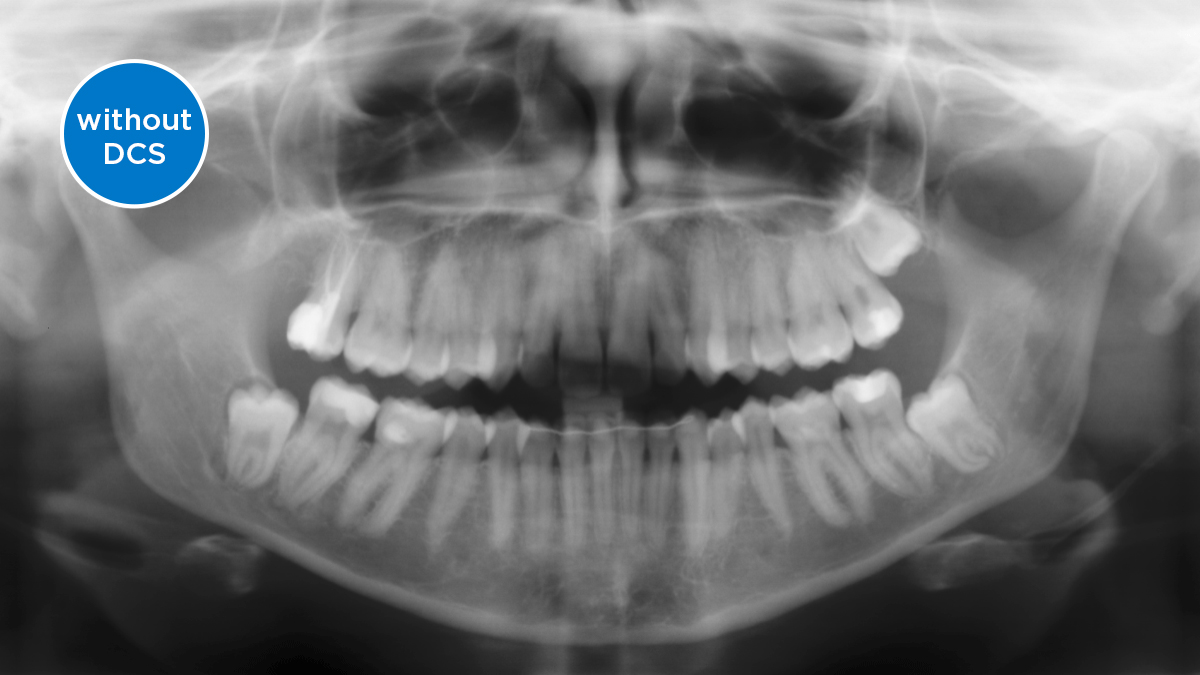

O Sensor de Conversão Direta (DCS) revolucionou o padrão de imagens panorâmicas. Os raios X são convertidos diretamente em sinais elétricos. Assim, não há perda de sinal por conversão de luz, como ocorre nos sistemas convencionais. O resultado: imagens com alto nível de nitidez e contraste, mesmo com baixíssima dose de radiação. Para obter informações de diagnóstico precisas para embasar o tratamento direcionado.

A imagem abaixo mostra uma radiografia panorâmica com e sem a tecnologia DCS. Usando a seta, arraste o controle pela imagem para ver a diferença que o sensor de conversão direta faz na qualidade da imagem e nas possibilidades de diagnóstico.